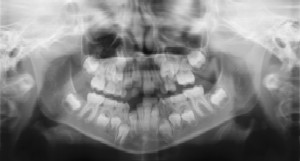

Radiographs (X-Rays) are a vital and necessary part of your child’s dental diagnostic process. Without them, certain dental conditions can and will be missed.

Radiographs detect much more than cavities. For example, radiographs may be needed to survey erupting teeth, diagnose bone diseases, evaluate the results of an injury, or plan orthodontic treatment. Radiographs allow dentists to diagnose and treat health conditions that cannot be detected during a clinical examination. If dental problems are found and treated early, dental care is more comfortable for your child and more affordable for you.

The American Academy of Pediatric Dentistry recommends radiographs and examinations every six months for children with a high risk of tooth decay. On average, most pediatric dentists request radiographs approximately once a year. Approximately every 3 years, it is a good idea to obtain a complete set of radiographs, either a panoramic and bitewings or periapicals and bitewings.